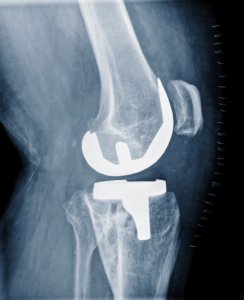

進行期:手術(人工関節置換術など)が必要になる場合もあります

最近では、こうした従来の治療に加えて PRP療法やエクソソーム療法といった再生医療 が選択肢に入るようになってきました。

再生医療は、膝の軟骨をできるだけ温存し、痛みを和らげることを目指す方法として注目されています。